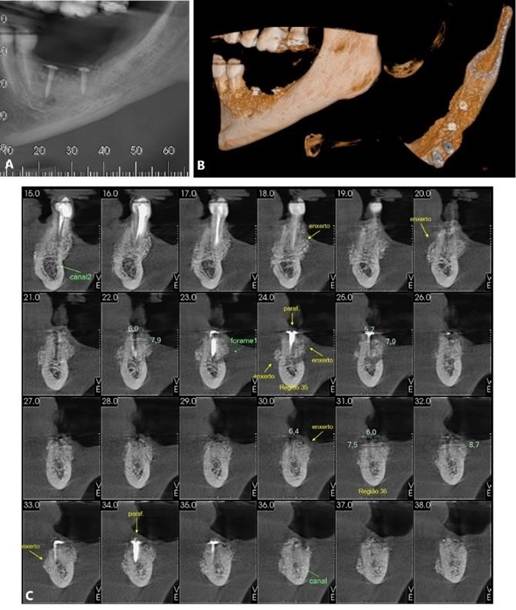

Foram solicitados exames complementares, incluindo radiografia panorâmica e tomografia computadorizada, para avaliação precisa da região anatômica, permitindo a quantificação da espessura e altura óssea (Figura 01. A-D). O plano de tratamento consistiu pela instalação de implantes ultrashort ARCSYS (FGM, Joinvile – SC, Brasil) 4,3 mm x 5,0 mm.

Figura 01. A – D) Exames de imagem complementares evidenciado aspecto inicial da região atrófica na maxila superior direita (área do elemento dental 16).

Figura 05. Exames de imagem da região inferior direita. A) Vista panorâmica. B) Reconstruções tridimensionais. C) Cortes transversais oblíquos.

Figura 06. Exames de imagem da região inferior esquerda. A) Vista panorâmica. B) Reconstruções tridimensionais. C) Cortes transversais oblíquos.